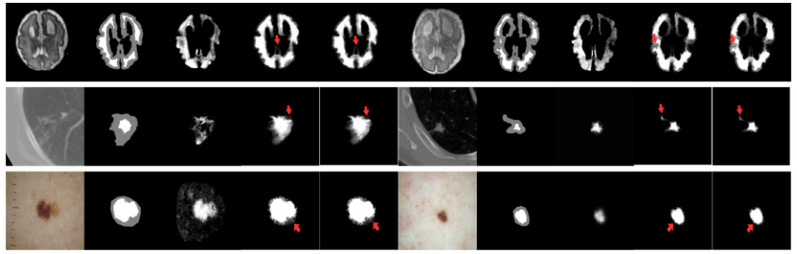

研究团队在实验三中构建了弱先验测试场景,将该方法与包括深度学习(DIM[7]等)在内的强先验方法以及其他弱先验方法(PDMS[8]等)进行了对比。弱先验测试场景的构建方式如下:从某个特定的医学图像数据集中随机抽取与自然图像数据集等量图像,组成一个新的测试数据集。在进行抠图遮罩预测时,仅提供三分图作为输入。

实验结果表 2表明,在仅提供Trimap的弱先验条件下,微搜索进化优化医学图像抠图算法在均方误差和梯度误差上,优于大多数对比方法。可视化结果(图 4)也显示,该方法能更准确地恢复前景与背景极其相似的模糊边缘区域。 表 2 弱先验测试场景中抠图预测指标对比

图 4 有无微搜索策略的抠图预测结果可视化对比